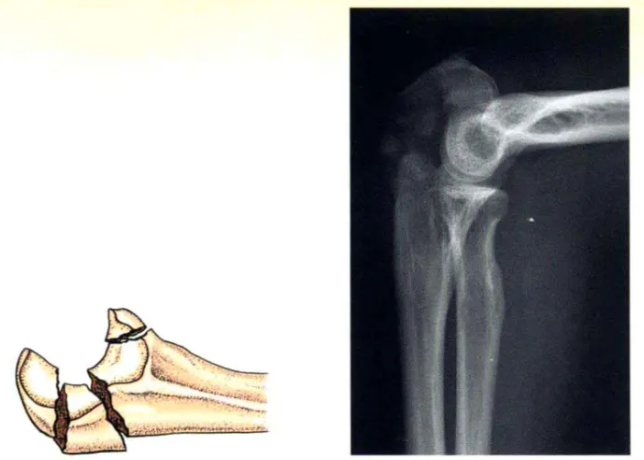

A型(xing):簡單(dan)橫形骨折(zhe)

A型(xing):張力帶固定的經典類(lei)型(xing),接(jie)骨板和螺釘固定也顯(xian)示有(you)效。